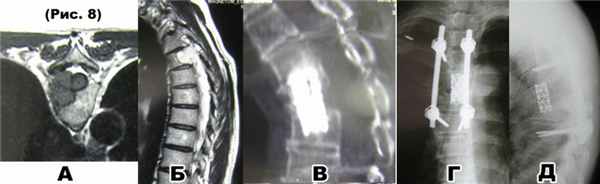

а) и б) МРТ: опухолевое образование(смешанная гемангиома) поражает тело, корень дуги Th4 позвонка справа и распространяется в позвоночный канал, сдавливая спинной мозг;

в) КТ и R-граммы после декомпрессивно-стабилизирующей операции: корпорэктомия, педикулэктомии справа и ламинэктомияTh4, корпородезTh3-Th5,транспедикулярная фиксацияTh3-Th6 позвонков;